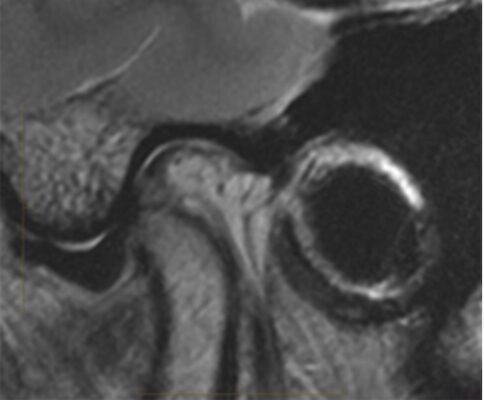

- MRI: là tiêu chuẩn vàng để lượng giá mô mềm trong TMJD. MRI có ưu điểm phân tích đĩa khớp, mô sau đĩa và các hệ cơ, cấu trúc dây chằng xung quanh theo ba mặt phẳng. MRI nên được xem xét khi có các triệu chứng lâm sàng bao gồm đau và tiếng lục cục khi vận động hàm hoặc nếu nghi ngờ có ung thư. MRI có độ nhạy 95% và độ đặc hiệu 88% khi so sánh với nội soi khớp để đánh giá TMJD.